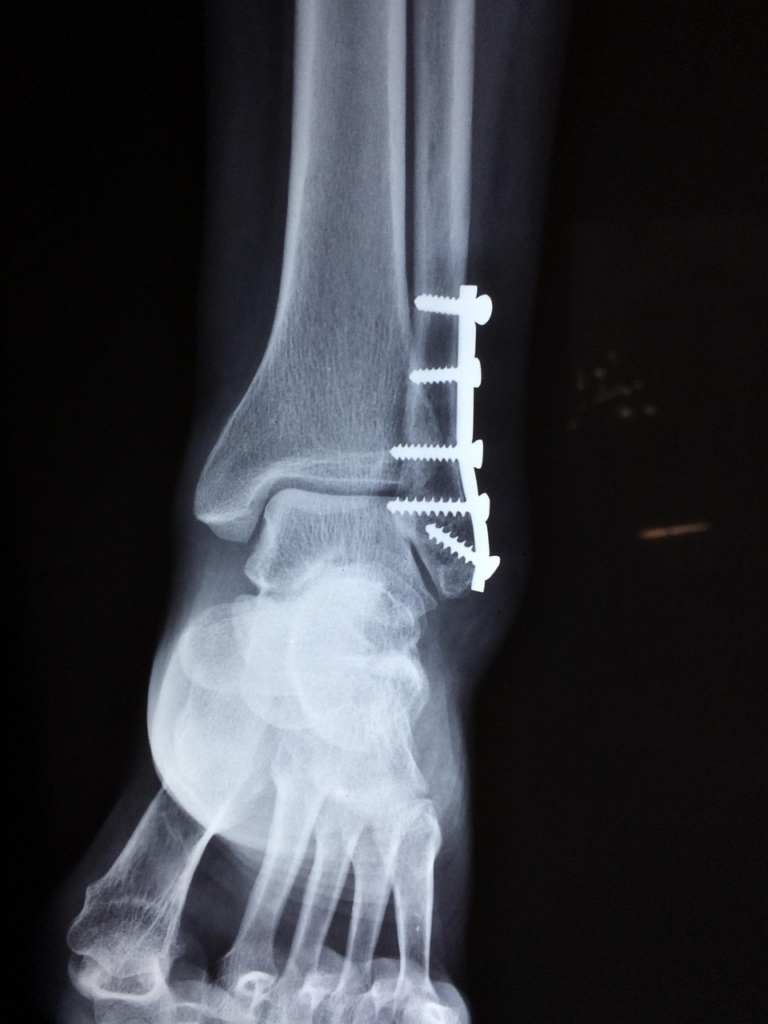

발목 골절 수술은 부러진 뼈를 금속판이나 나사로

정확한 위치에 고정해 주는 치료입니다.